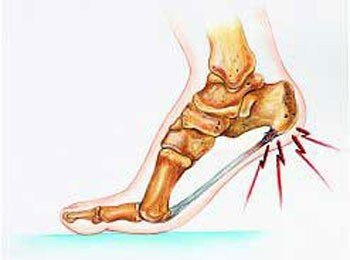

再来看这简单有效的示意图。

刚才说了,脚底板横着的那条是跖底筋膜,而脚后面竖着的那条,就是跟腱了。也就是武侠小说里自废武功所说的“脚筋”。

这个跟腱可以看到也是终止于跟骨上,它也会出现前面类似跖底筋膜一样的微小撕裂、劳损、炎症等等,就不再赘述了。再者,严格来说,跟腱周围疼痛并不在我们所说的跟痛症范畴,我们医学上讲的跟痛症,主要还是集中在脚跟底部附近的疼痛,而跟腱痛则在脚后的后侧甚至踝关节的后侧,位置偏上。但是有一点一定要注意,有一些风湿科的疾病,如强直性脊柱炎,这是一种侵犯肌腱韧带起止点的疾病,所以有的强直性脊柱炎的病人会出现跟腱的疼痛、病人自己说就是脚后跟疼,而这有时候偏偏是一部分强直性脊柱炎病人早期唯一的症状。所以,在门诊,只要是十几岁,二十来岁的,尤其是瘦长身材的男孩来说自己脚后跟疼,我一般都会让他们排查下强直性脊柱炎。毕竟这个病早期发现还是很有治疗意义的。